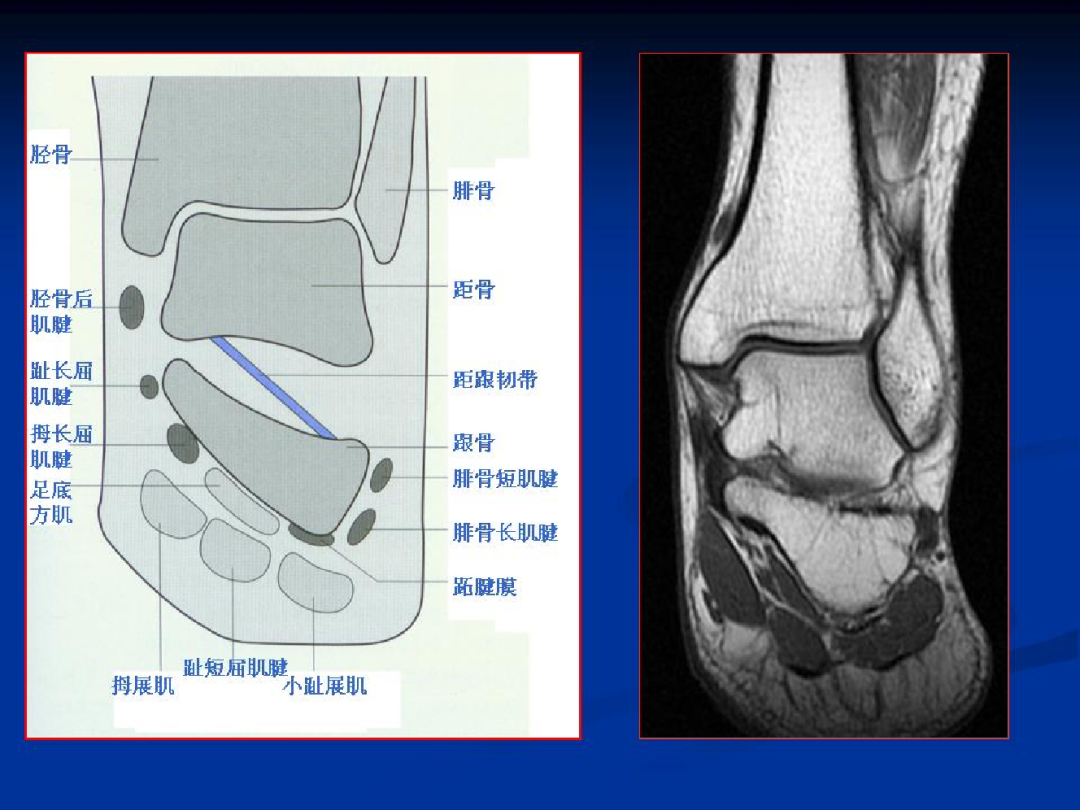

踝关节解剖及损伤MRI表现

骨性结构

踝关节:全身持重关节

组成:由胫骨下端和内、外踝构成的踝穴及距骨体共同组成。

包括:骨、韧带、肌腱、软骨、滑膜等结构

韧带

内侧三角韧带:胫距前、后韧带,胫跟韧带,胫舟韧带;

外侧韧带:距腓前韧带,距腓后韧带,跟腓韧带;

韧带复合体:胫骨前、后韧带,胫腓骨间韧带;

肌腱

外侧:腓骨长肌腱、腓骨短肌腱

内侧:胫骨后肌腱、趾长屈肌腱、踇长屈肌腱

前方:胫骨前肌腱、趾长伸肌腱、踇长伸肌腱

后方:跟腱